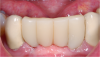

Fig. 14 and Fig. 15 Immediate postoperative photographs of two implants placed through tissue punch, chairside temporaries, and immediate-load implants.